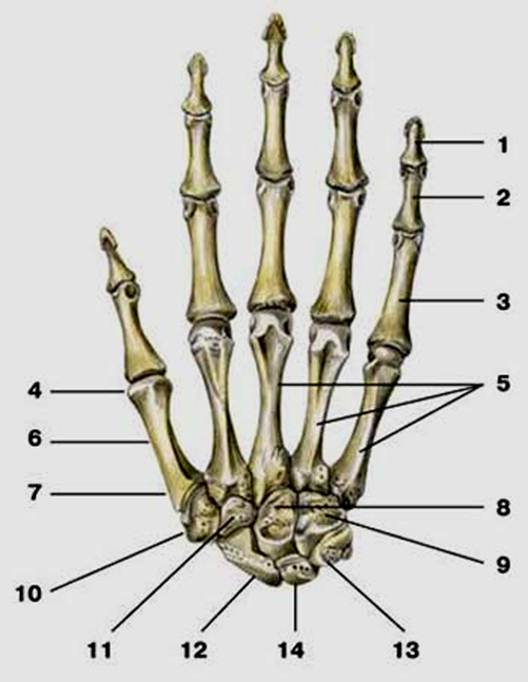

S: Числом 10 обозначена os trapezium (латинский язык).

S: Цифра 5 обозначает ossa metacarpi (латинский язык).

S: Цифрой 8 обозначена os capitatum

S: Числом 12 обозначена os scaphoideum

S: Числом 13 обозначена os triquetrum

S: Цифра 3 указывает на phalanx proximalis

S: Цифра 2 указывает на phalanx media

S: Цифра 1 указывает на phalanx distalis